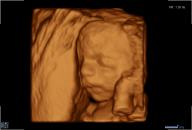

3D/4D-Ultraschall für Schwangere

Seit März 2019 steht ein neues 3D/4D-Ultraschallgerät für faszinierende Eindrücke von Ihrem Baby zur Verfügung.

Außer den Fotos können auch 3D/4D Viedeoclips gemacht und auf einem USB-Stick gespeichert werden. So können die Bilder und Clips jederzeit angesehen werden.